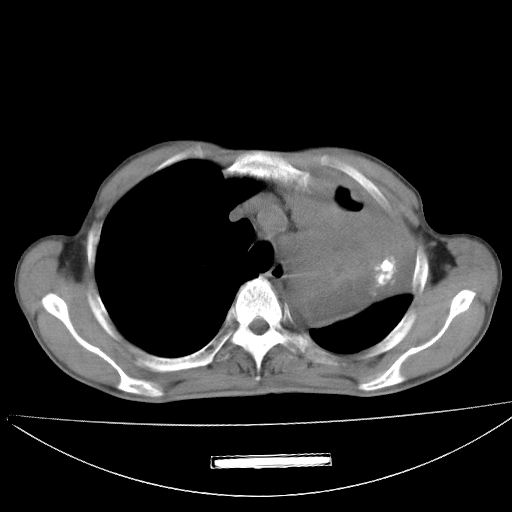

以下是引用杀毒软件在2009-4-28 17:58:00的发言:[br]考虑----左肺慢性肺脓肿形成继发上叶含气不良---抗炎后复查---待排肿瘤所致[br][br][本贴已被 杀毒软件 于 2009-4-28 18:01:26 修改过]